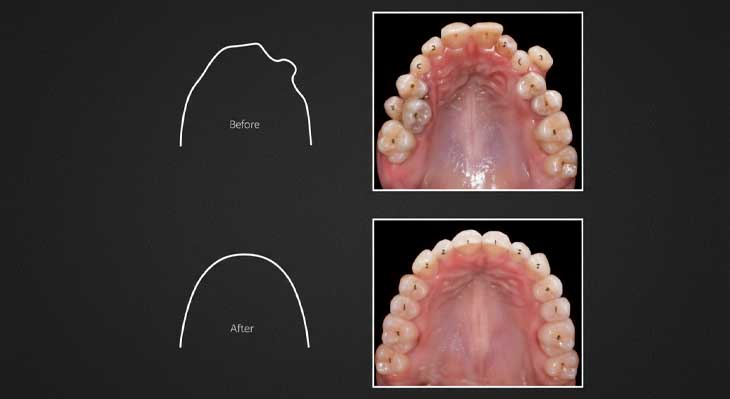

درمان شلوغی دندان ها با ارتودنسی بدون کشیدن دندان

شلوغی یا بهم ریختگی دندان ها یکی از شایع ترین دلایلی است که افراد را به سمت درمان ارتودنسی سوق می دهد. این مشکل زمانی رخ می دهد که فضای کافی در قوس فکی برای قرارگیری منظم تمام دندان ها وجود نداشته باشد. در گذشته، راه حل رایج برای رفع این کمبود فضا، کشیدن برخی از دندان ها (معمولاً دندان های آسیاب کوچک) بود. اما امروزه، فلسفه درمان به سمت روش های محافظه کارانه تر تغییر کرده است. ارتودنسی بدون کشیدن دندان با استفاده از تکنیک های مدرن، به جای حذف دندان، تلاش می کند تا فضای مورد نیاز را از راه های دیگری ایجاد نماید.

این رویکرد نه تنها تمام دندان های سالم بیمار را حفظ می کند، بلکه اغلب منجر به ایجاد یک لبخند پهن تر و زیباتر می شود. با حفظ تمام دندان ها، ساختار و نیم رخ صورت نیز بهتر حمایت می شود و از فرورفتگی احتمالی لب ها در آینده جلوگیری می گردد. متخصص ارتودنسی با ارزیابی دقیق عکس های رادیوگرافی و مدل های دندانی، میزان کمبود فضا را محاسبه کرده و بر اساس آن، مناسب ترین تکنیک را برای جابجایی و چرخش دندان ها بدون نیاز به کشیدن انتخاب می کند. این روش نیازمند دانش، مهارت و برنامه ریزی دقیق از سوی متخصص ارتودنسی است.